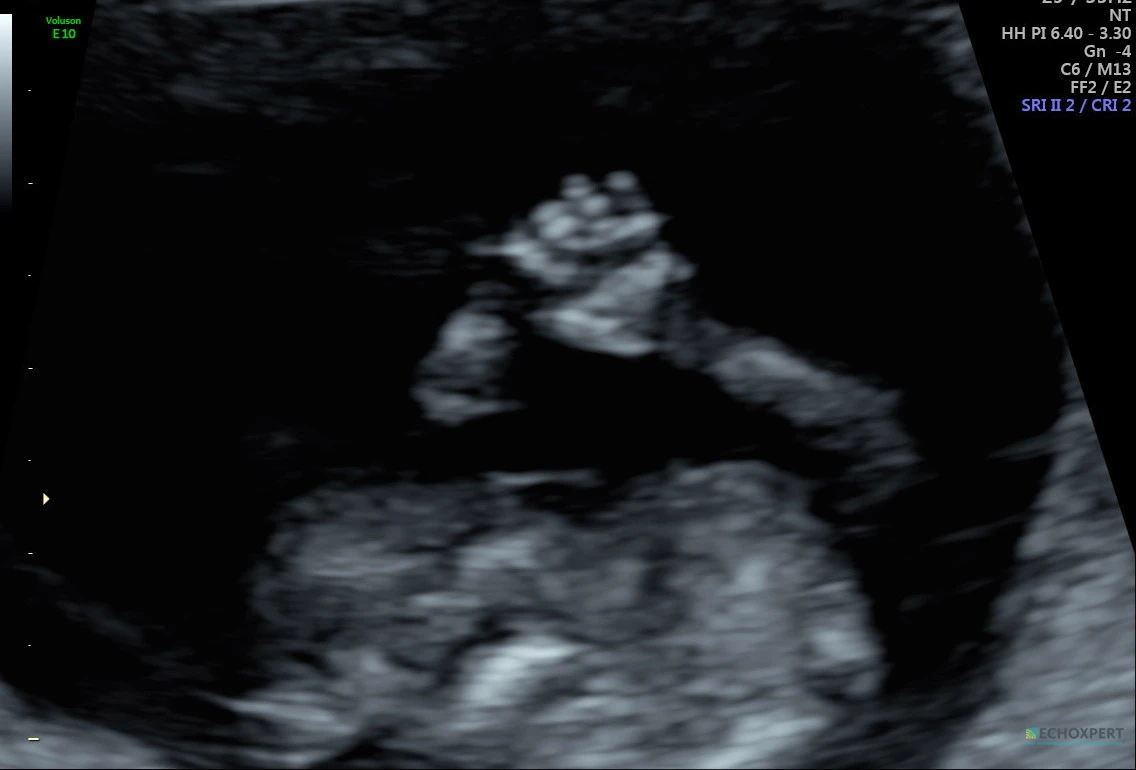

프로젝트 화면으로 아기의 옆모습이 보였다. 어디가 코인지, 턱인지 제법 구분도 잘 되는 데다 몸속에서 빠른 속도로 뛰는 심장도 선명하게 볼 수 있었다. 아, 좋은 초음파 기계라는 게 이런 거였구나. 그전까지 언제나 조금씩 흐릿하게 보여서 온갖 상상력과 공간지각력을 동원했어야 했던 지난 초음파 검진들이 순식간에 지나갔다.

“목 투명대도 2.3mm로 정상이고, 머리-엉덩이 길이도 7.2cm니까 아주 잘 자라고 있네요.”

그리고 초음파 선생님은 이곳저곳을 비춰가면서 심장이 잘 뛰고 있는지, 팔다리, 손발은 다 잘 발달하고 있는지, 뇌는 예쁘게 만들어지고 있는지, 탯줄과 태반은 잘 자리를 잡았는지 등을 약 20분간 꼼꼼하게 검사했다.

“보세요, 아기가 손을 흔드네요. 기지개도 켜고요.”